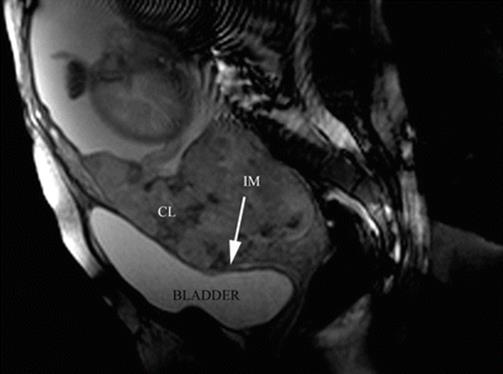

Fig. 14.6

Sagittal T2 image: confluent lagoons (CL) are evident near to uterine-bladder interphase. The uterine segment myometrium is interrupted (IM) or extremely thinning. In this area, the placenta reaches to the uterine serosa